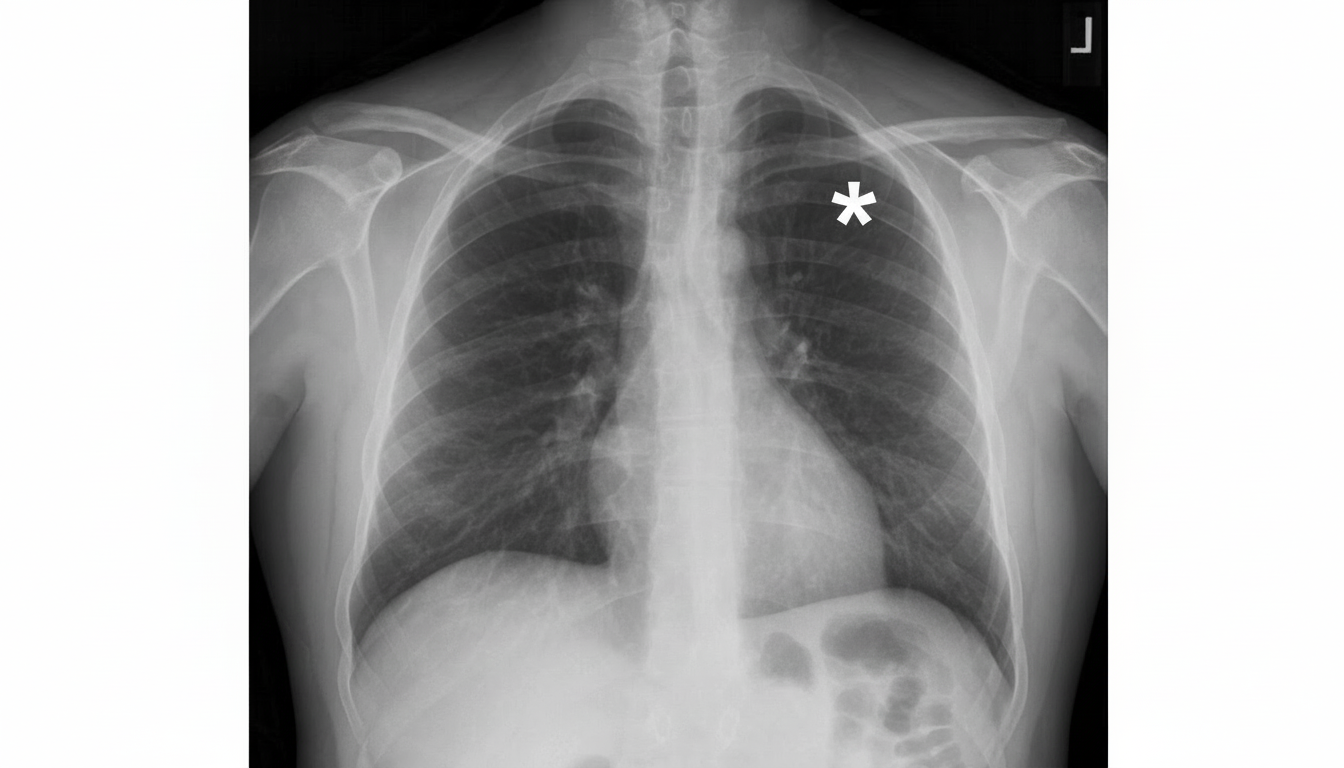

The asterisk is denoting towards which of the following structures?

Explanation: ***Right anterior 4th rib*** - The **4th rib** can be identified by counting down from the **clavicle** (which overlies the 1st rib) or by using the **sternal angle** as a landmark at the level of the 2nd rib. - **Anterior ribs** appear more horizontal and are located in the **anterior chest**, distinguishable from posterior ribs by their orientation and position. *Right clavicle* - The **clavicle** appears as a horizontal bone structure at the **top of the chest** and overlies the 1st rib. - It has a characteristic **S-shaped curve** and is positioned much higher than the 4th rib level. *Right posterior 5th rib* - **Posterior ribs** appear more **oblique** and **vertically oriented** compared to anterior ribs on a PA chest X-ray. - The **5th rib** would be located one level below the 4th rib, and posterior ribs are typically seen in the **lateral chest** areas. *Major fissure* - The **major fissure** appears as a **linear opacity** extending from the hilum toward the **costophrenic angle**. - It represents the boundary between the **upper and lower lobes** and has a completely different radiographic appearance from bony structures.